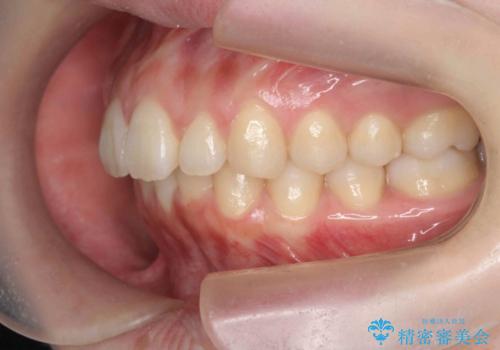

マウスピースで出っ歯感の改善

- 上の前歯が出ている感じを治したい、と矯正治療を希望され来院されました。

上顎歯列の突出感を改善すべくIPRを行い、下顎歯列を小さくすることで前歯の角度を大きく是正します、。

下顎歯列は元々前歯が1本少なく小さなアーチでしたが、下顎に合わせ上顎歯列もIPRを行い小さくすることで出っ歯感を大きく改善することが出来ました。